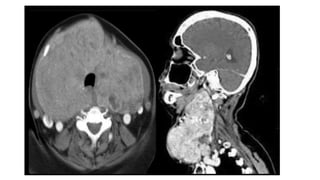

• #24 Ectopia may be suprahyoid , infrahyoid and, intratracheal, or mediastinal, with the latter related to an unusual exaggeration of inferior descent of the thyroglossal duct beyond the usual tract

• #25 Contrast-enhanced computed tomography study of a patient with an infrahyoid ectopia of the thyroid gland shown by the arrows in all images. In (B), there is thyroid tissue not attached to the main ectopic glandular tissue, demonstrating the potential for all migrational abnormalities of the thyroid gland to result in disconnected lateral ectopic tissue (arrowheads). In (C), there are multiple small cysts within the ectopic tissue, suggesting that such ectopic tissue can develop abnormalities that might occur in normally positioned thyroid tissue (arrowheads).